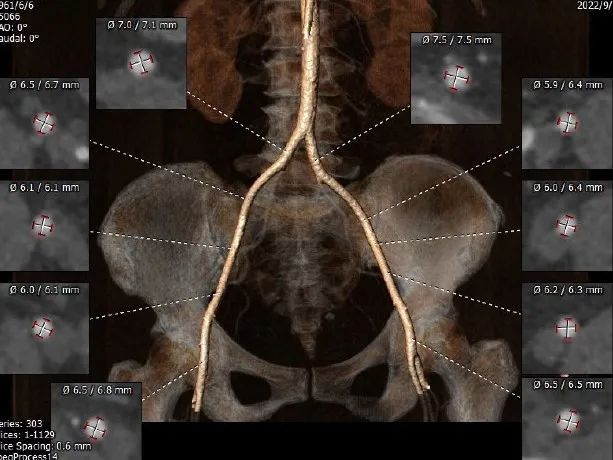

CT测量

瓣环周长:67.2mm

LVOT周长:67.5mm

瓣环上4mm:66.3mm

瓣环上6mm:65.4mm

左冠开口高度:13.2mm

右冠开口高度:11.7mm

瓣环角度:59°

升主动脉周长:109.9mm

入路情况

• 瓣环周长为67.2mm,均径20.9mm,LVOT 周长为67.5 mm,均径20.2 mm;

• 瓣上4mm/6mm周长分别为66.3mm和65.4mm;

• 瓣环及流出道无钙化,瓣膜存在移位风险;

• 冠脉开口低,存在冠脉堵塞风险;

• 两侧股动脉入路无迂曲、无钙化,分叉高度均可。左侧血管平均最小内径为6.1mm,右侧血管平均最小内径为6.1mm。